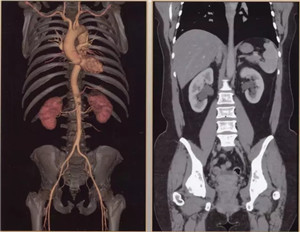

扫描范围最大:16厘米宽体宝石探测器,心脏、颅脑、肝脏等单器官检查一次扫描就可实现全覆盖;